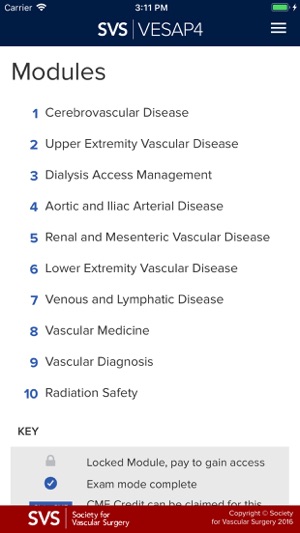

The VESAP4 mobile app is a self-assessment program designed to meet the Maintenance of Certification requirements of the Vascular Surgery Board of the American Board of Surgery for continuing medical education credits and MOC self-assessment credits. The app allows users to use VESAP4 offline.

VESAP4 has over 500 questions and includes detailed discussions and references for each question. You may use this product in Learning Mode as often as you like. You will not earn CME credit or MOC self-assessment credit in Learning Mode; however, you will be able to review a rationale for the responses and will access available abstracts in PubMed.

VESAP4 is an invaluable aid for vascular surgeons in preparing for the qualifying, certification, and recertification examinations in vascular surgery and to remain current in the specialty of vascular surgery and endovascular therapy. Vascular residents and fellows will find it a useful study aid for their ABSITE or VSITE examinations.

Interventional radiologists, cardiologists, vascular medicine specialists, and allied health care professionals focusing on vascular diseases may use VESAP4 self-assessment to keep abreast of the current practice of vascular surgery and endovascular therapy.